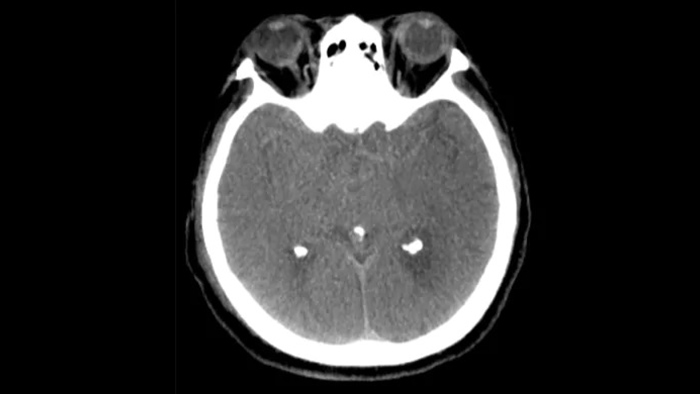

Tres SmartCT

Visualización similar a la de un TAC

SmartCT Soft Tissue  genera una visualización similar a la de un TAC convencional de tejido blando y respalda el diagnóstico de accidentes cerebrovasculares de tres maneras. Una exploración sin contraste ayuda a la detección de cambios isquémicos tempranos. Una exploración en fase temprana ayuda a identificar la oclusión proximal. Una exploración con contraste en fase tardía respalda la detección de colaterales.

Revisión de hemorragias periprocedimiento

SmartCT Soft Tissue

Utilice las imágenes obtenidas mediante SmartCT Soft Tissue (similares a TAC convencional) en el paquete Neurovascular para comprobar el éxito del tratamiento y las hemorragias.